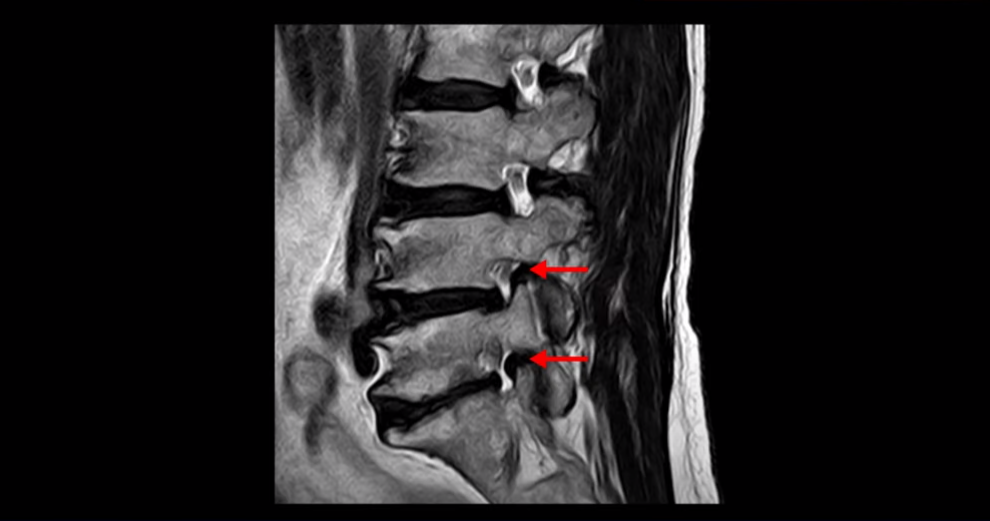

협착증은 노화 때문에 생기는 질환입니다. 나이가 들수록 노화와 퇴행 때문에 신경 구멍이 조금씩 좁아집니다. 이분도 신경 구멍이 좁아져 있습니다. 보시다시피 척추 여러 마디가 퇴행되어 있고

척추관도 좁아져 있고

오른쪽 신경이 빠져나가는 추간공도 두 마디가 좁아져 있지만

좁아진 게 많이 심해 보이지는 않습니다. 그런데 이분이 갑자기 아프게 된 건 불과 2-3달 전입니다. 그럼 1년 전에 전혀 안 아팠을 때 MRI를 찍었다면 최근에 아플 때 찍은 MRI와 많이 달라 보일까요? 정답은 거의 차이가 없다입니다. 아프기 전이나 아픈 후나 MRI로 보이는 신경 구멍의 크기가 같다면 그럼 왜 갑자기 2-3달 전에 극심하게 아픈 증상이 생겼을까요? 그건 약해진 허리 주변 근육에 문제가 생겼기 때문입니다. 어떤 근육 문제가 이런 다리 방사통을 만들까요?